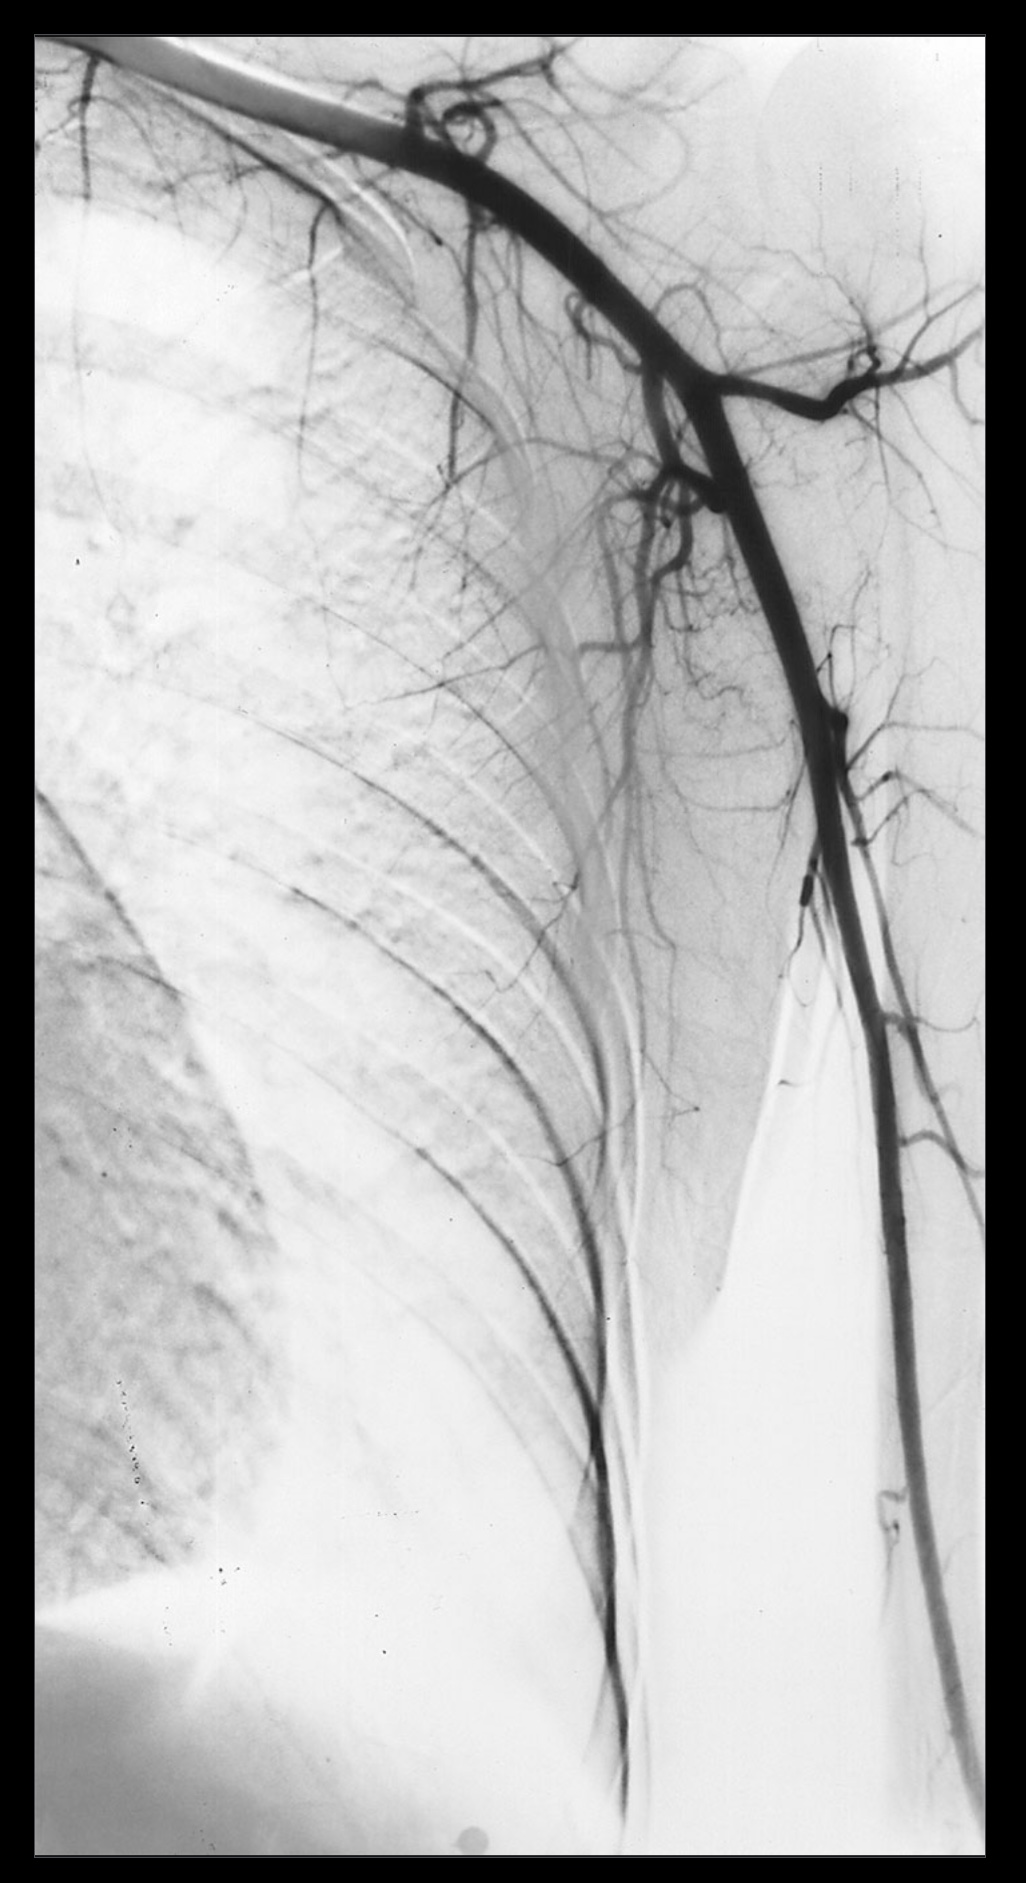

Essay answers are to be written in prose during the assigned examination time. Please write your answers in the spirit of communicating to a colleague or a knowledgeable patient. Demonstrate your understanding of anatomy more so than your rote memorization. If you draw a figure, please describe what you have drawn using anatomical terminology. Our aspirations for you are that you write the cookbook, not follow it.

1. A patient complains of shoulder pain and difficulty rotating their arm. An ultrasound reveals edema within the spinoglenoid notch, which could explain weakness in external rotation at the glenohumeral joint. Describe the normal scapular and shoulder anastomosis, including all arterial branches involved and their relationship to any ligaments, scapula borders, and intermuscular spaces. If the axillary a. is ligated immediately distal to the thyrocervical trunk, would this edema affect active collateral circulation? (If yes, explain.) Also, include a brief (2-3 sentences) explanation for why edema within the spinoglenoid notch might result in weak external/lateral rotation of the shoulder.